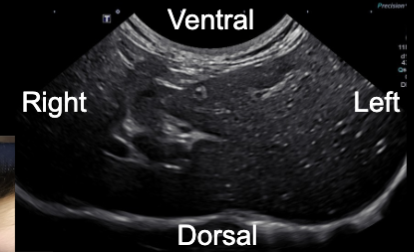

Transverse

Isoechoic

(same brightness): blends with surrounding tissues

Hypoechoic

(darker): weaker reflection

ex. many soft tissues

Anechoic

(black): no echoes

Example: fluid (like cysts or blood vessels)